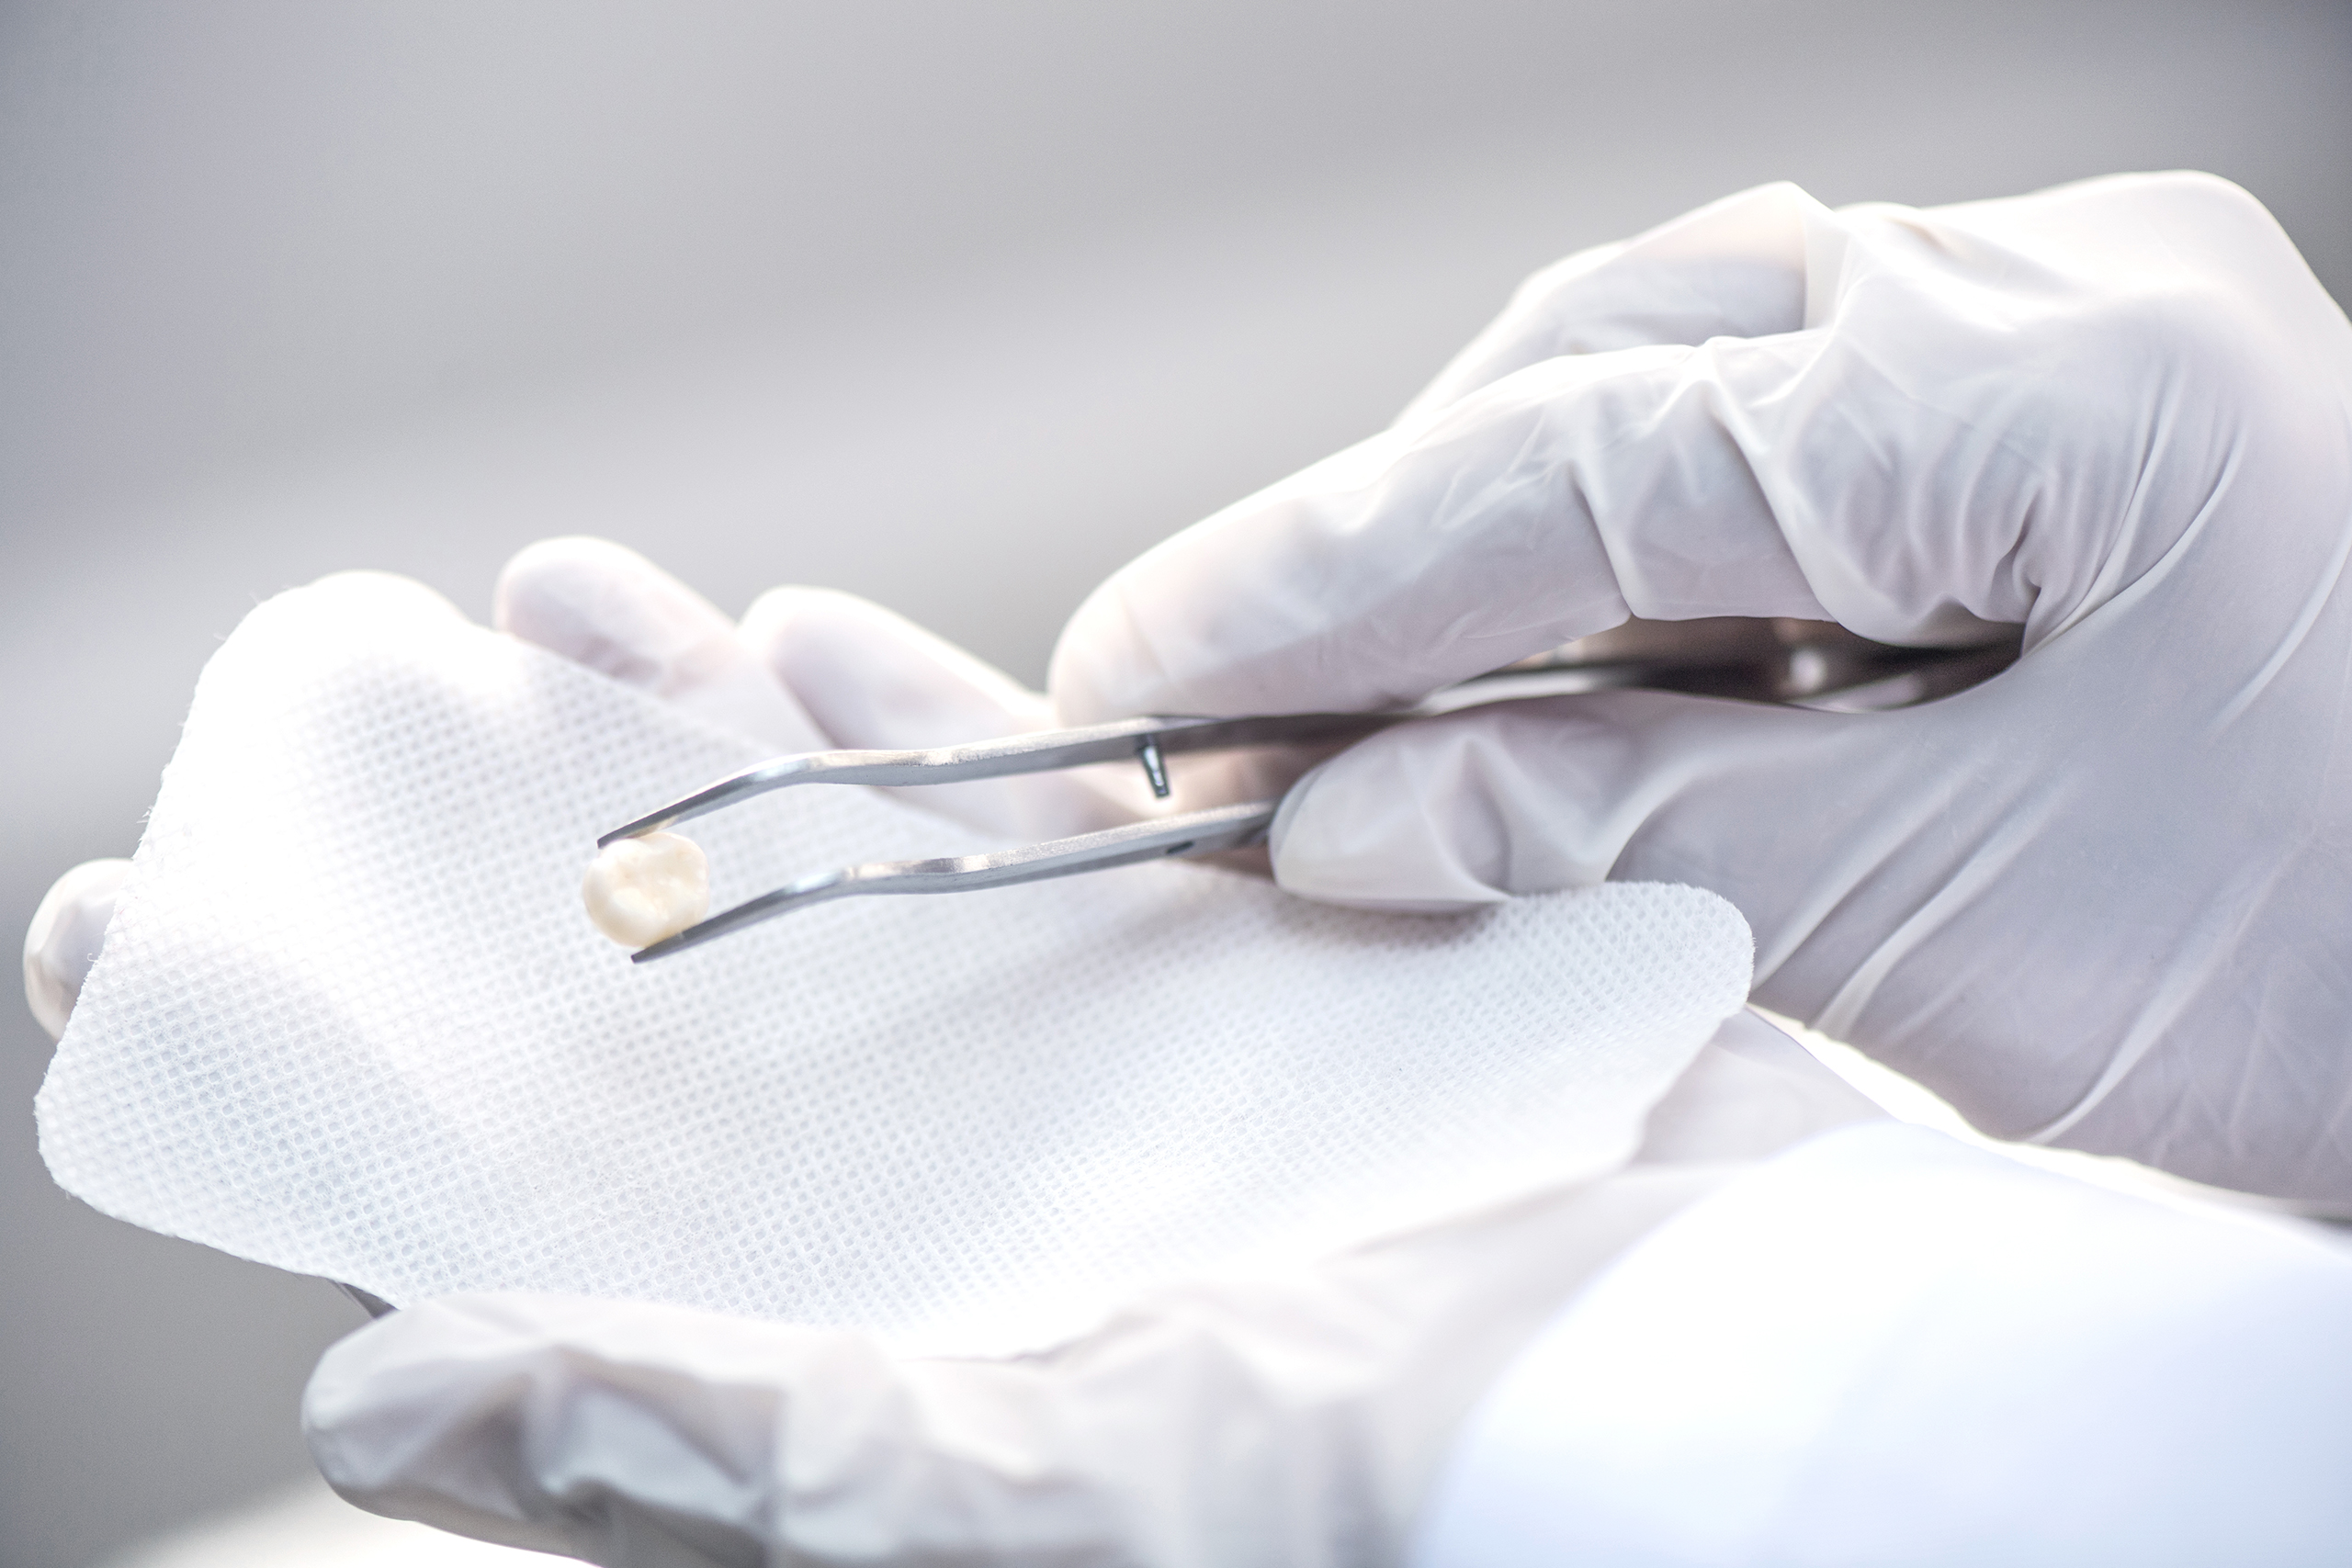

Dentistry

Family Dentistry